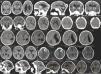

A tabela 1 resume os achados clínicos e radiológicos. Foi possível acessar as digitalizações da tomografia computadorizada (TC) da cabeça de 95 neonatos confirmados com microcefalia e 21 casos descartados. Alguns achados radiológicos são apresentados na figura 3. As digitalizações da TC revelaram calcificações intracranianas em 78/95 (82,1%) dos casos confirmados de microcefalia e 1/25 (4,8%) dos casos descartados (p <0,001). Entre as crianças confirmadas com calcificações, duas apresentaram calcificações dos núcleos basais (não mostrados). Dez (10,5%) dos casos confirmados apresentaram alterações do espectro de lisencefalia‐paquigiria, sete (7,4%) apresentaram hidrocefalia e cinco (5,3%) apresentaram agenesia do corpo caloso. Além disso, 40 neonatos foram submetidos a ultrassom (US) transfontanelar (20 casos confirmados e 20 descartados). Entre os neonatos com microcefalia confirmada, 11 (55%) apresentaram ventrículos cerebrais dilatados e três (15%) apresentaram diagnóstico ultrassonográfico de hidrocefalia. O US transfontanelar detectou seis (30%) crianças com calcificações.

1 Digitalizações da tomografia computadorizada da cabeça dos casos confirmados de microcefalia no Estado do Piauí; 1; Brasil, 2015‐2016.

A. Calcificações na interface entre a substância branca e cinza e nas regiões do núcleo da base. Ectasia ventricular moderada associada a paralelismo dos ventrículos laterais, sugere disgenesia do corpo caloso; 1; Deformidade do esqueleto e redução do volume do cerebelo devido a atrofia, com aumento do espaço do fluido cerebrospinal da fossa posterior.

B. Pequenas calcificações no intervalo entre a substância branca e cinza; 1; Escassez dos sulcos corticais, configura alteração do espectro de lisencefalia.

C. Pequenas calcificações no intervalo entre a substância branca e cinza, linear e puntiforme; 1; Escassez dos sulcos corticais, configura alteração do espectro de lisencefalia.

D. Pequenas calcificações no intervalo entre as substâncias branca e cinza, linear e puntiforme; 1;1; Assimetria dos hemisférios cerebrais com acentuação dos sulcos corticais e redução do volume do hemisfério esquerdo devido a atrofia, com ectasia compensatória consequente do ventrículo lateral.

E. Leve paralelismo dos ventrículos laterais, sugere disgenesia do corpo caloso.

F. Pequenas calcificações puntiformes na interface entre a substância branca e cinza e calcificação grosseira no lóbulo frontal esquerdo. Escassez dos sulcos corticais com poucos sulcos rasos, configura alteração do espectro de lisencefalia. Leve paralelismo dos ventrículos laterais, sugere disgenesia do corpo caloso; 1; Deformidade do esqueleto na região frontal alta.

G. Pequenas calcificações puntiformes no intervalo entre a substância branca e cinza e a região periventricular. Escassez dos sulcos corticais, configura alteração do espectro de lisencefalia. Redução volumétrica do cerebelo; 1; Deformidade do esqueleto.

H. Pequenas calcificações puntiformes na interface entre a substância branca no lobo frontal esquerdo. Escassez dos sulcos corticais, além dos sulcos rasos, configura alteração do espectro de lisencefalia. Expansão dos espaços de fluido extra‐axial, mais evidente nas fossas temporais. Redução do volume do hemisfério direito com ectasia compensatória do ventrículo lateral direito.